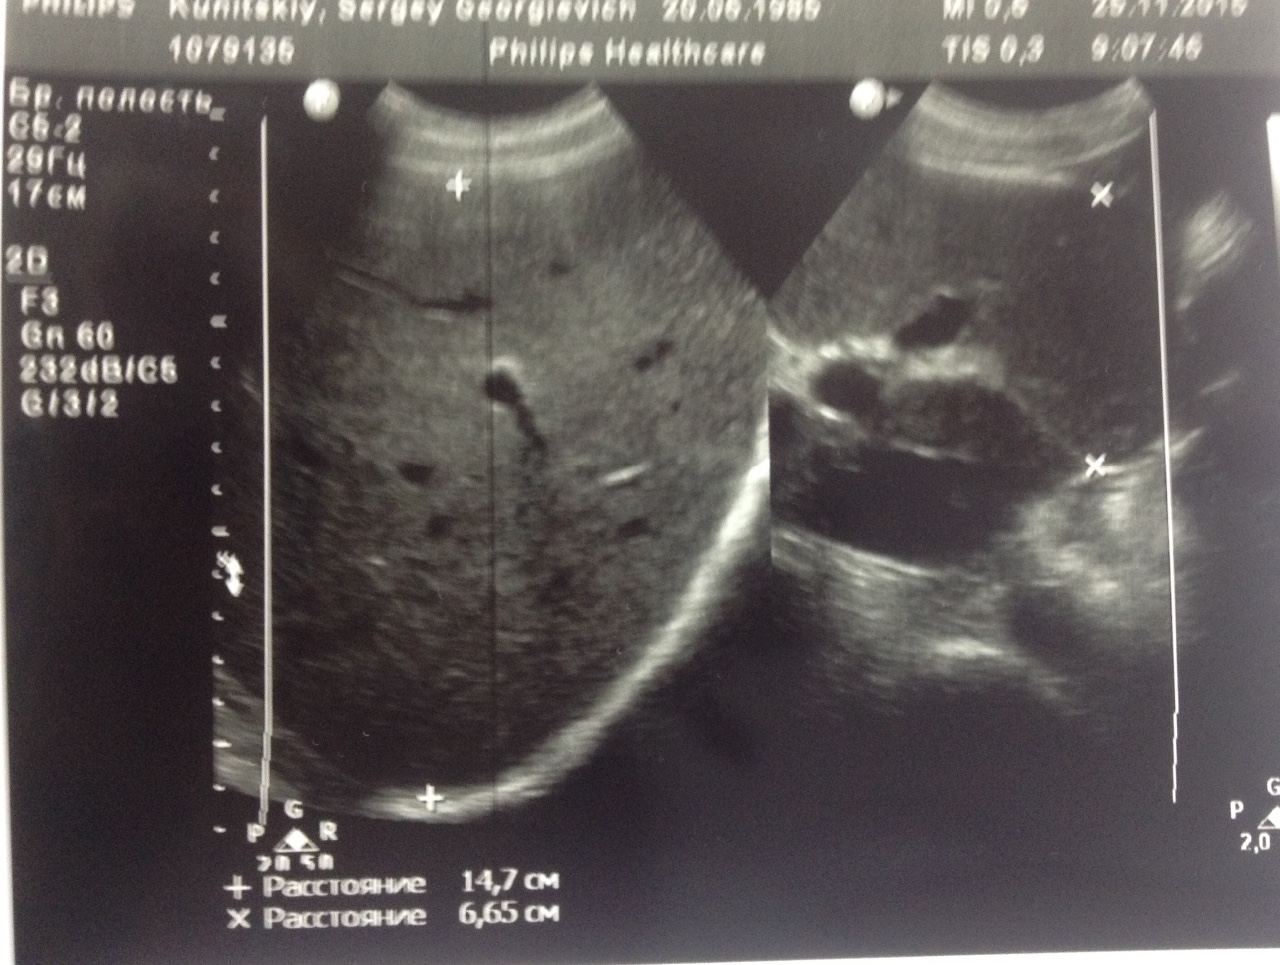

Как выглядит доля Риделя на УЗИ печени